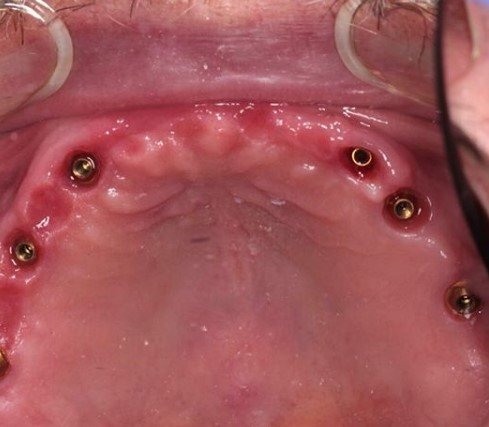

Протезирование на мультиюнитах

Полная вторичная адентия зубов . Протезирование на мультиюнитах .